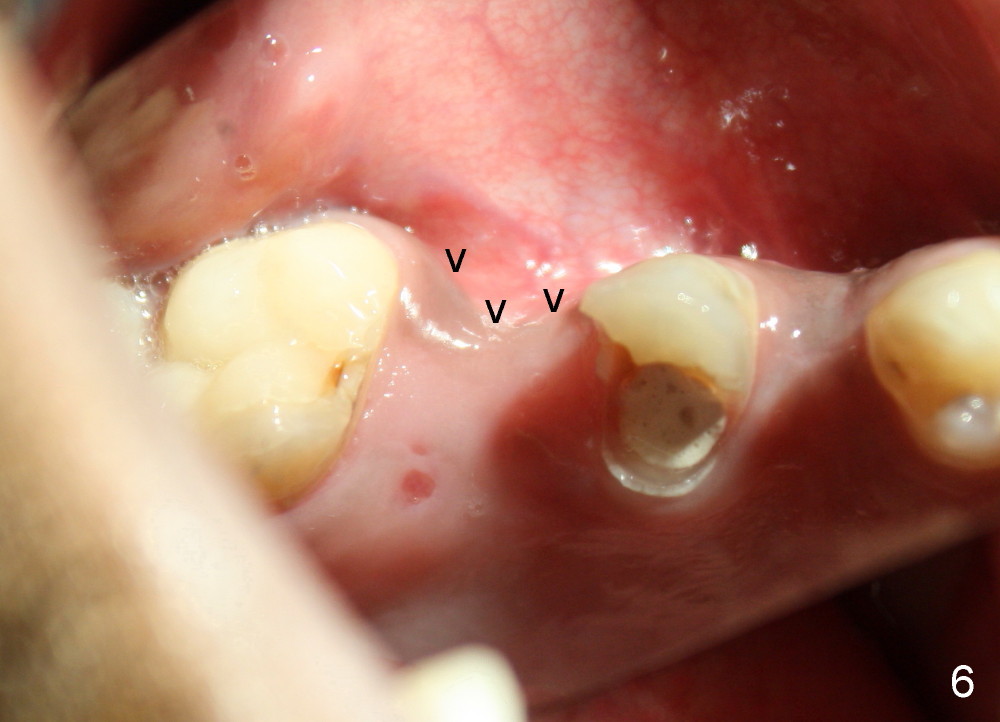

The socket looks empty two months post-extraction (Fig.4 S). Bone appears to re-grow in the socket 9 months after extraction (Fig.5 S), but the buccal plate is severely atrophic and concave (Fig.6 arrowheads). When an incision is made, the socket feels soft. Osteotomy is created by bone expansion (round tapered osteotomes (RT) 2,3,4 mm). Drilling is done once, using 3.5x17 mm tapered drill when the larger RTs meet resistance near the sinus floor. Tapered taps are used to continue to expand the osteotomy (4.5 (Fig.7), 5.0 and 6.0x20 at the depth of 17 mm). Finally 6.0x17 mm implant is placed with insertion torque more than 60 Ncm (Fig.8). The buccal plate is less concave with bone expansion and implantation (Fig.9 arrowheads). Without immediate implant, bone resorbs quick, which makes delayed implantation difficult.